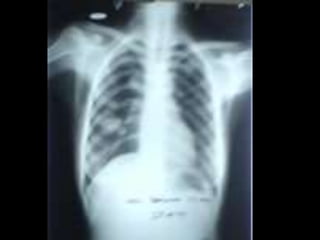

• C’est untéléthorax de face objectivant une opacité de tonalité hydrique siégeant au niveau du champ pulmonaire inférieur gauche, de forme ovalaire, mesurant 5cm de grand axe, de plage hétérogène par la présence de broncho gramme, de limites plus ou moins nettes et les contours sont irréguliers. • En appliquant le signe de la silhouette, l’opacité n’efface pas le bord gauche du médiastin donc elle est de topographie postérieure. Ailleurs on note une opacité hilaire gauche irrégulière. L’index cardio-thoracique est normal, les culs de sac pleuraux sont libres, pas de lésions osseuses visibles. • Conclusion : syndrome de comblement alvéolaire évoquant un cancer broncho-pulmonaire, métastase pulmonaire unique Diagnostic différentiel : abcès du poumon, tumeur bénigne. • CAT : TDM thoracique, échographie abdomino-pelvienne et scintigraphie osseuse Fibroscopie bronchique